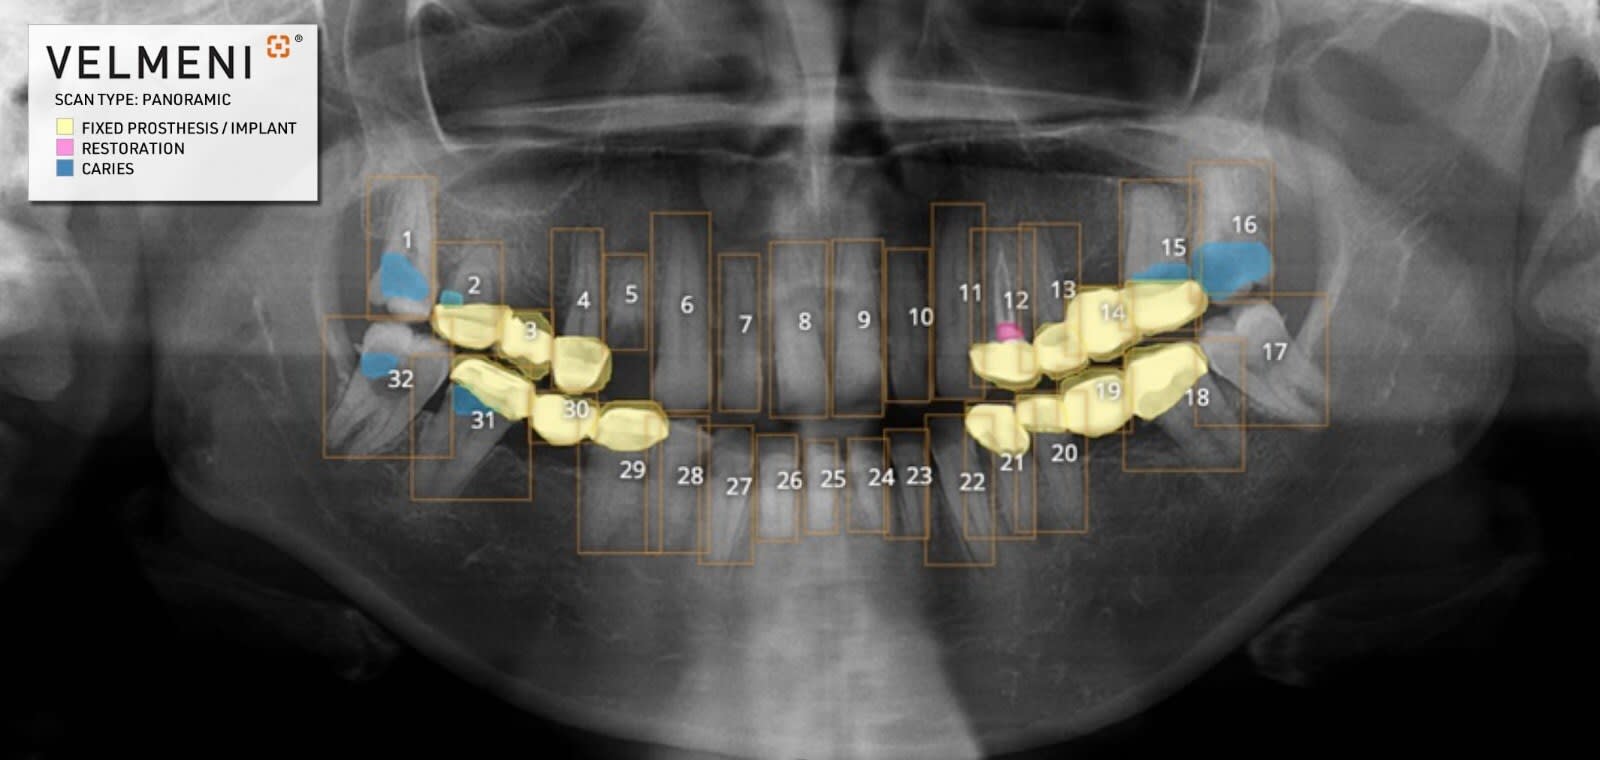

VELMENI for DENTISTS (V4D) assists dentists in the detection of dental caries, fillings/restorations, fixed prostheses, and implants in digital bitewing, periapical, and panoramic radiographs of permanent teeth in patients 15 years of age or older.

VELMENI is the first dental AI approved by the FDA to detect pathologies in panoramic X-Rays. VELMENI for DENTISTS adds its US FDA clearance to existing Canadian MDEL and New Zealand MEDSAFE clearances.

Many dental conditions are difficult to see in dental X-Rays. The VELMENI AI reveals numerous pathologies, increasing diagnostic accuracy.

Pictured: VELMENI-PAN-Findings